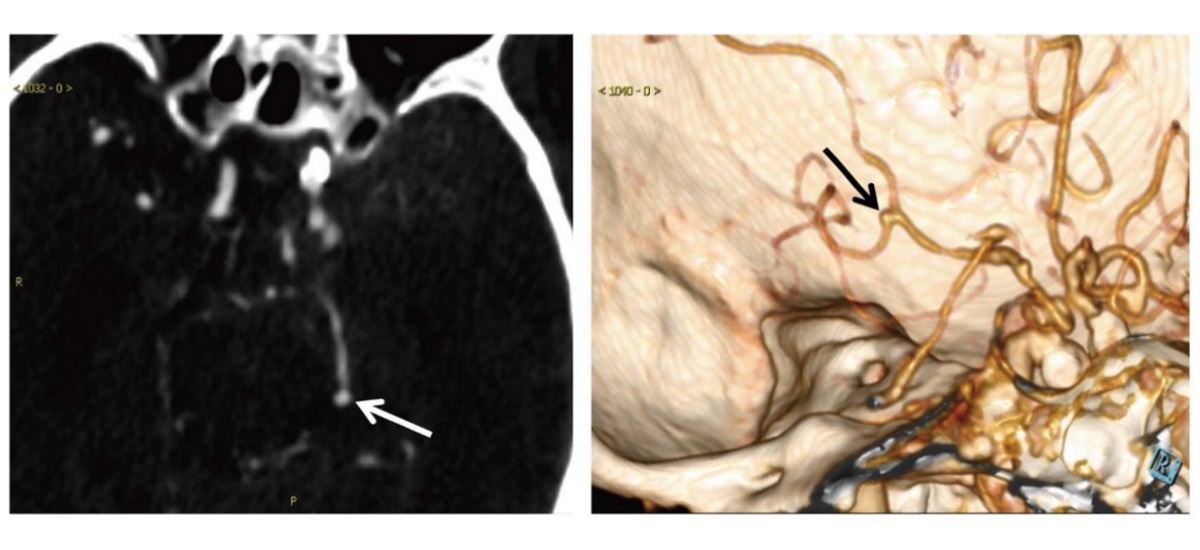

CT를 이용해 혈관을 시각화하는 CT 혈관조영술은 뇌동맥류를 검출하기 위한 1차 영상검사다. 그러나 뇌동맥류는 CT 촬영으로도 확인이 어려울만큼 작은 크기다. 또 복잡한 혈관구조는 일부 뇌동맥류를 잡아내지 못하는 가능성을 동반한다.

이에 동제대 연구팀은 의료진의 눈보다 정확히 뇌동맥 질환을 진단할 수 있는 딥러닝 알고리즘을 개발했다. 연구팀을 이끈 시롱 교수는 “뇌동맥류는 방사선 영상에서 의료진이 간과하고 넘어갈 수 있는 작은 병변 중 하나”라며 “인간의 눈이 보지 못한 중요한 질환을 AI가 대신 찾아낼 것”이라고 말했다.

이후에도 알고리즘 기능은 점차 향상돼 10mm 이상의 동맥류 검사에서 정확도 100%에 도달했다. 이 알고리즘은 또한 1차 방사선 촬영 시 인간 의료진이 확인하지 못한 8개의 새로운 동맥류를 발견하는 데 성공했다. 이 중 6개는 3mm보다도 작은 크기였다.